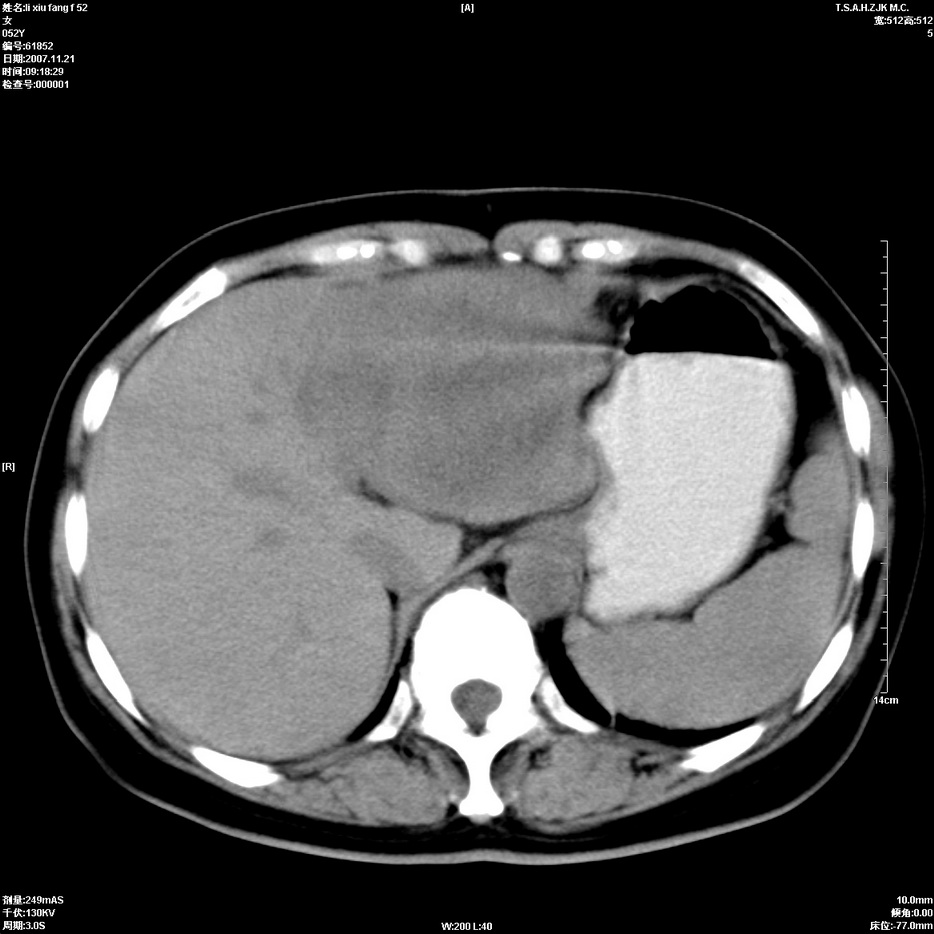

标题: CT12858:女,52岁,胎甲球蛋白861肝左叶占位,肝癌。下腔静 [打印本页]

标题: CT12858:女,52岁,胎甲球蛋白861肝左叶占位,肝癌。下腔静

肝左叶巨大低密度灶肿块,增强符合快进快出表现,有动静脉交通支;静脉期,下腔静脉内有充盈缺损,afp明显升高,支持肝癌并下腔静脉癌栓形成。

支持楼主   门静脉主干及左支癌栓形成

以下是引用拾荒者在2008-4-15 22:57:00的发言:[br]肝左叶巨大低密度灶肿块,增强符合快进快出表现,有动静脉交通支;静脉期,下腔静脉内有充盈缺损,afp明显升高,支持肝癌并下腔静脉癌栓形成。